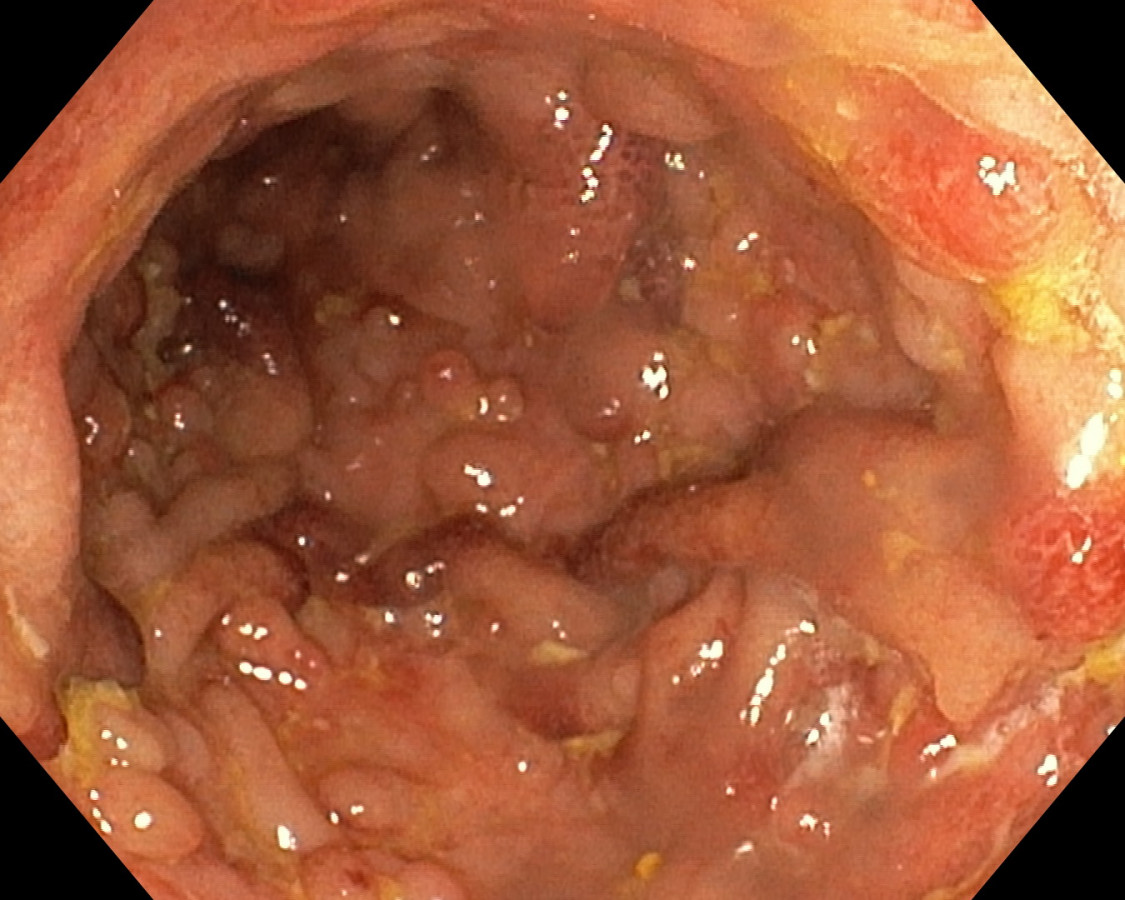

Polypóza u pacienta s ulceróznou kolitídou

Pacient s UC - dg. od r. 2009 ako pankolitída, od 4/2010 pri imunosupres. th. kompletná remisia ochorenia, už vtedy pseudopolypózne štádium, noncompliance, kontrola až pri relapse v r. 2017. Odvtedy +/- chodí na kontroly. 07/2023 relaps, systémové kortikosteroidy, ATB, s efektom - 9/2023 pankolonoskopia - pravostranne nález dobrý, ľavá strana síce bez aktivity ochorenia, aj histolog. remisia, ale polypózne št. hlavne v sigme - foto - dysplázia zachytená nebola. Bude ťažké odsledovať KRCA v tomto teréne. Dalo by sa uvažovať o chirurgickej liečbe ? Ďakujem.

U nemocných s UC je výskyt zánětlivé polypózy, kterou rozumíme přítomnost více než deseti zánětlivých polypů, relativně častý. Je odrazem těžce probíhající zánětu. Zánětlivé polypy nemají sami o sobě potenciál maligní degenerace a v tomto ohledu není potřeba je kontrolovat nebo odstraňovat. Mnohočetné zánětlivé polypy však znesnadňují průběh dispenzárních koloskopických prohlídek, protože významně omezují přehlednost po sliznici a detekci dysplastických změn. Druhý negativní dopad vícečetných zánětlivých polypů je u udržování aktivního zánětu a elevaci hodnot fekálního kalprotektinu. U nemocných s mnohočetnými zánětlivými polypy v rektu a rekto-sigmatu mohou být persistující tenesmy a intermitentní krvácení vyvolány právě jejich přítomností. V těchto případech je endoskopicky odstraňujeme.